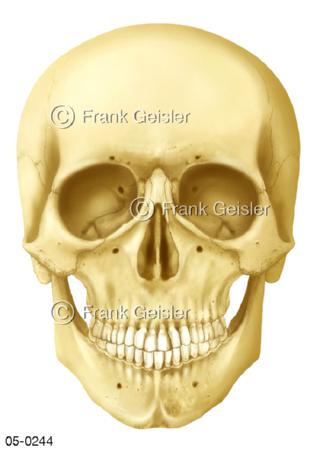

Bildergalerie Skelettsystem

Bilder zum Skelettsystem zeigen die Stützstruktur des menschlichen Körpers, die Knochen, eine besonders harte Form des Bindegewebes und Stützgewebes, welche das menschliche Skelett bildet, die Knochen des Stammes, der Extremitäten sowie der Gelenke